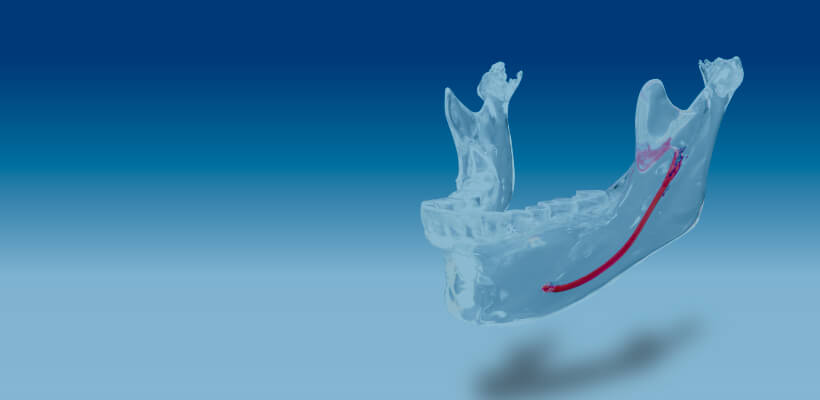

Preoperative simulation

Facial contouring,

Inferior alveolar canal

The osteotomy line can be drawn while checking the position of the inferior alveolar nerve canal.